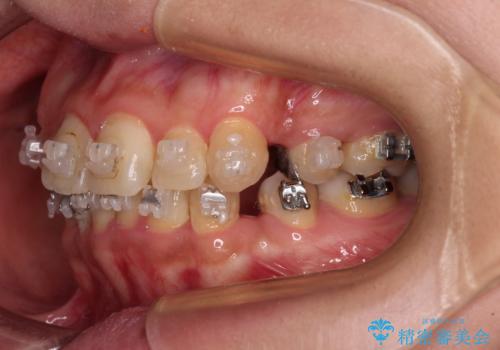

当院では、張り替える必要のある部位は張り替えることで継続することとし、抜歯スペースを閉じていくように治療を行うこととしました。